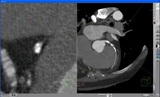

Slab MIPでは蛇行した血管を素早く観察できる。

CT for PCI Learning Centerは,角辻 暁氏(大阪大学/野崎・名古屋・大垣徳洲会病院)がCourse Directorを務め,山崎慶太氏(大阪大学),奥津匡暁氏(野崎徳洲会病院),亀谷良介氏(名古屋徳洲会総合病院),黒田 忠氏(大阪大学)をインストラクターとして,3日間で計9コマが実施された。ハンズオンセミナーでは,ザイオソフト社のソフトウエア「zioTerm」を使用。同社では今年3月から,2D画像処理が可能なzioTermをインターネット経由で無償で配布している。2D,MPR,3Dの機能に加え,血管の観察に適した“Slab MIP”などの機能も搭載されている。Slab MIPはシンプルな操作方法で,初めてでも短時間で操作を習得することができる。

16日16時からのセミナーでは,山崎慶太氏がインストラクターを務め,最初にzioTermの簡単な操作法を練習した上で,1)Slab MIP法の基礎,2)冠動脈のスクリーニング―冠動脈長軸・短軸画像評価,3)症例検討―プラークの検出,プラークの分布・質的評価,石灰化の評価,ステント内評価,CTO(慢性完全閉塞病変)の評価をテーマに,実臨床で役立つワークステーションの活用法を実践した。初めは操作にとまどいを見せていた参加者も,15分もすると画像の回転,拡大,CT値の違いで組織を色分けできるカラーマップなどの操作を習得し,いくつかの症例を対象に,実際に血管内がどのように評価できるかなどについて,PCIの画像と比較しながら確認した。